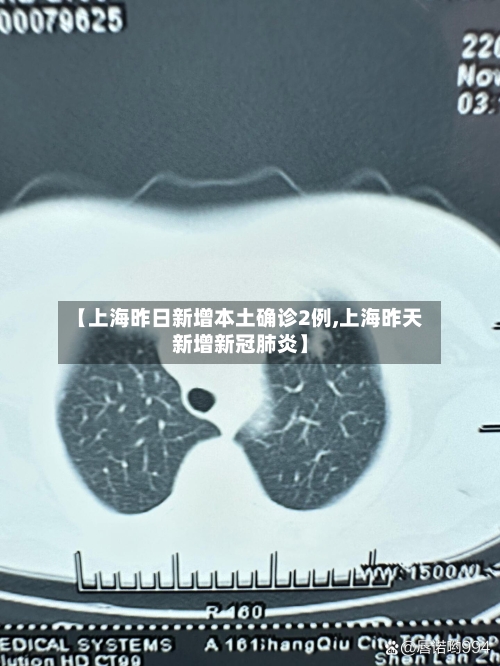

【上海昨日新增本土确诊2例,上海昨天新增新冠肺炎】

云南昨日新增确诊病例2例,详情公布〖壹〗、月26日0-24时,云南省新增本土确诊病例2例,分别来自瑞丽市和盈江县。具体情况如下:病例发现地点与情况瑞丽市:在集中隔离点密接人员核酸检测中发现1例。这表明当地对密切接触者采取了集中隔离措施...